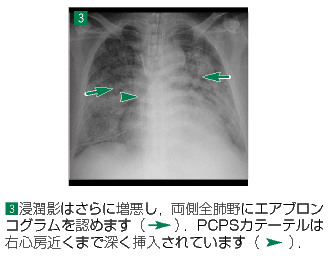

▲143ページ 経時的変化 3番目の画像内および所見欄(2007/2/5)

※矢印の追加と位置の修正(下は修正済みの画像です)

| ● |

|